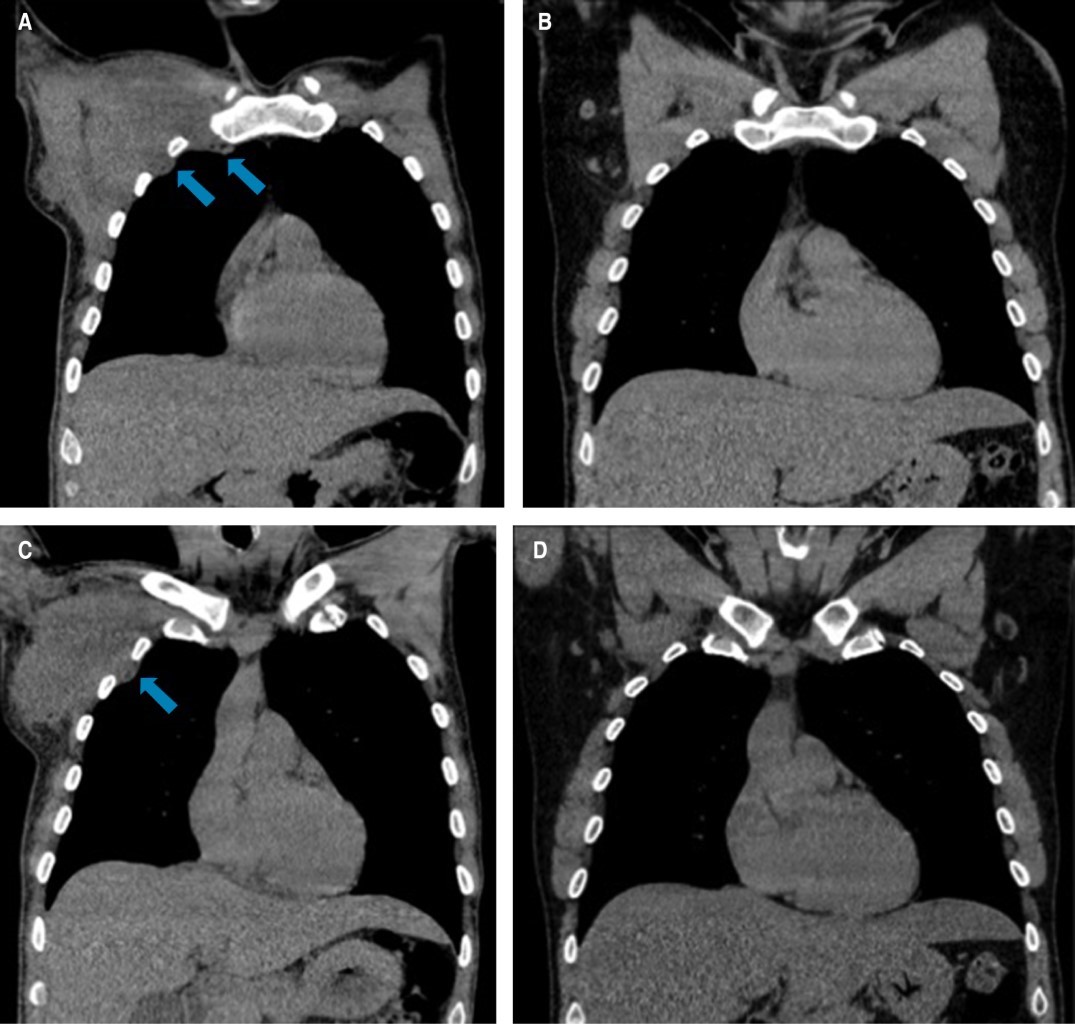

Debido a la localización, se envía al Servicio de Cirugía Cardiotorácica donde a la exploración se observa masa fija a pared torácica derecha, dolorosa a la palpación, principalmente en extensión hacia la axila, de consistencia firme y sin evidencia de circulación colateral en piel. Se valora tomografía de tórax contrastada donde se reporta tumoración de aspecto infiltrativo a nivel de tejidos blandos en región axilar derecha con arteria nutricia proveniente de arteria axilar, dicha lesión es irregular con dimensiones aproximadas de 8.8 cm en su eje cefalocaudal, 11 cm latero-lateral y 7.5 cm en su eje rostroventral, coeficiente de atenuación en fase simple de 20 unidades Hounsfield (UH) y al paso de contraste con captación de 37 UH. Dicha lesión no invade estructuras óseas adyacentes, únicamente se evidencia el desplazamiento de pectoral menor, subescapular y serrato anterior ipsilateral. En región axilar ipsilateral se identifican adenopatías de morfología redonda y captación significativa al contraste. Además, se identifican adenopatías que conservan su hilio graso prevasculares, pretraqueales e hiliares. Se concluye: tumoración infraclavicular/axilar derecha con infiltración a ganglios regionales adyacentes al mismo (Figuras 1 y 2). Es por esto que se toma biopsia con aguja de corte que reporta tejido fibroconectivo.

Un mes después del inicio de los síntomas, el paciente acude a consulta refiriendo reducción de la tumoración de forma espontánea, donde a la exploración física no se observa ni se delimitan masas a la palpación, por lo que se realiza tomografía de tórax en diferentes cortes donde no se observan remanentes de la tumoración torácica o de las linfadenopatías (Figuras 1 y 2).

Figura 1